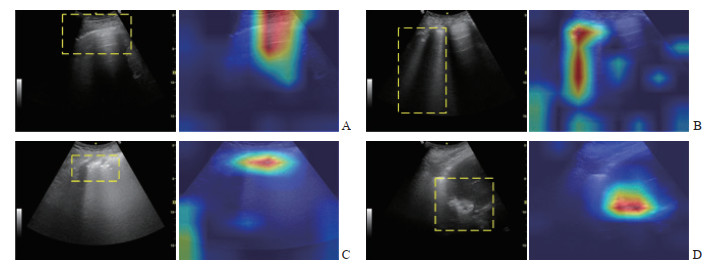

为进一步验证改进后的FastViT模型在肺超声图像评分任务中的有效性及对关键征象区域的关注能力,本研究采用梯度加权类激活映射(gradient-weighted class activation mapping,Grad-CAM)方法对模型的判别依据进行了可视化分析。图 9为部分测试样本在改进FastViT模型中的Grad-CAM特征激活热图。从图中可以看出,改进后的FastViT模型能够较好地聚焦于肺超声图像关键征象所在区域,显示出较强的特征提取和判别能力。这一结果进一步验证了新型Stem结构在增强模型对关键区域感知能力方面的有效性,同时也提升了模型的可解释性。

图 9 改进FastViT模型在不同征象关注情况下的可视化结果Fig. 9 Visualizations of the improved FastViT model focusing on different ultrasound signsA: Continuous pleural line with the presence of A-lines; B: Presence of B-lines; C: Discontinuity of the pleural line; D: Pulmonary consolidation observed. FastViT: Fast hybrid vision Transformer.2.2 B线检测实验结果与讨论

图 9 改进FastViT模型在不同征象关注情况下的可视化结果

Fig. 9 Visualizations of the improved FastViT model focusing on different ultrasound signs

A: Continuous pleural line with the presence of A-lines; B: Presence of B-lines; C: Discontinuity of the pleural line; D: Pulmonary consolidation observed. FastViT: Fast hybrid vision Transformer.